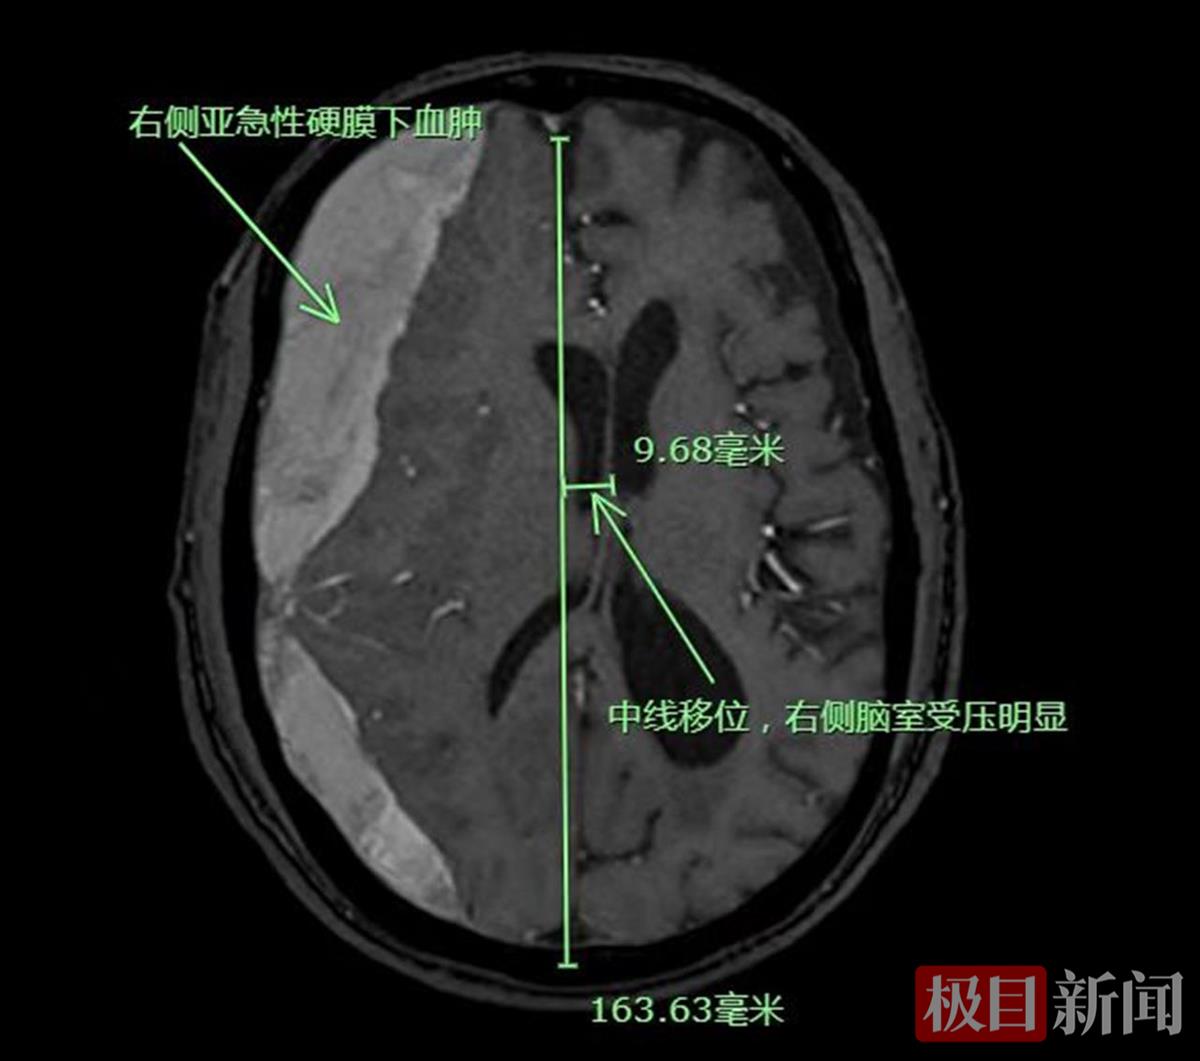

11月14日早上,81岁的宋爹爹突然感觉头痛和左侧肢体乏力伴行走不稳,于是,家人立即将宋爹爹带至家附近医院就诊,经检查头部CT提示右侧亚急性硬脑膜下出血,且出血量大,约有100毫升,并且伴有中线移位脑疝形成,需要尽快行手术治疗。由于病情十分危重,家人立即将宋爹爹转往武汉市普仁医院神经外科就诊。

核磁共振提示右侧亚急性硬脑膜下出血

“患者长期口服阿司匹林和三七粉,这两种药都可以让少量出血无法自行凝固,进而慢慢地出血逐渐增加,最终压迫到脑组织引起一系列症状。”武汉市普仁医院神经外科副主任医师罗宽解释称,理论上来说,这种伴有脑疝形成的亚急性硬脑膜下出血是有急诊手术指征的,需要尽快地手术清除血肿,解除血肿对脑组织的压迫,挽救患者的生命和功能。但由于患者长期口服了阿司匹林和三七粉,这两种药物都容易让手术中出现止血困难的问题,且患者本身高龄,心肺功能较差,这极大地提高了手术风险。由于当时患者意识状态还算清楚,生命体征还算平稳,综合考虑后向家属建议先卧床休息,减少活动,停止服用此类药物,待体内的药效代谢掉后,再进行手术治疗。”